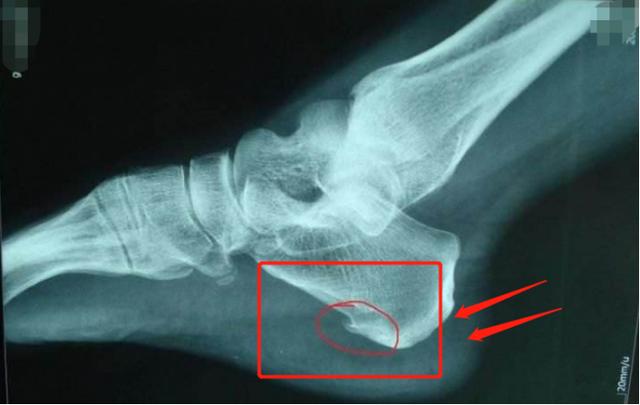

很多人可能习惯叫它骨刺、骨质增生,但它的医学名称其实是骨赘。风湿、关节炎或其它炎症、长期的磨损等原因都会刺激骨的代偿性生长,从而产生骨赘。比如下图就是一张典型的跟骨骨赘图片。

骨赘可以发生于腰椎、膝关节、脚后跟等部位,其中跟骨骨赘多发于中老年人群体。骨赘并不是引发疼痛的主要原因。只有出现骨赘压迫神经等情况时,才会引发疼痛。(部分患者可能会出现足底部的广泛性压痛。)